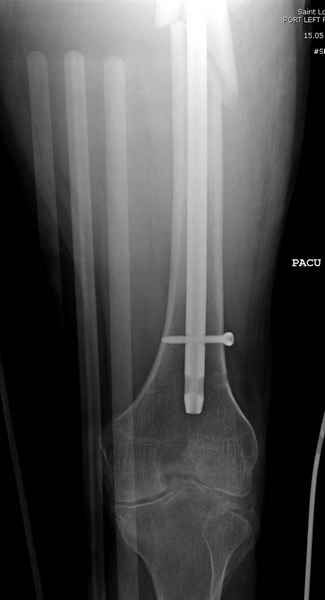

Среди русскоговорящих коллег Ортофорум стал одним из мест, где многие из нас черпают знания для решения своих ежедневных проблем в виде практических советов и обмена опытом. Кроме таких советов, Ортофорум стал источником новых познаний среди ортопедов, особенно по редко встречающимся состояниям в ортопедии. Продолжая традицию, я хотел бы представить редко встречающий случай перелома бедра у больного с гемофилией. Больному 42, гемофилия типа А, из истории упал с высоты около 1,5 метра, переправлен из другой больницы. По происхождению мексиканец, 10 лет назад по поводу артроза пр. коленного сустава в Мексике сделано протезирование, которое закончилось ампутацией выше коленного сустава. При поступлении бедро напряженное, сосудистых и неврологических расстройств нет. На рентгенограмме оскольчатый перелом бедра с вовлечением проксимальной спирали в шейку бедра. Хотели бы знать тактику ведения подобных больных и на что надо обратить внимание? Djoldas Kuldjanov, MD Department of Orthopedic Surgery St. Louis University Medical Center

Учитывая, что случай ургентный, больной поступил вечером, не стали делать вытяжение и срочно провели операцию по фиксации перелома бедра антеградным штифтом Versa Nail от DePuy.

Для профилактики дальнейшего раскола в шейке предварительно во время проксимального рассверливания спереди и сзади провели временные спицы, которые в дальнейшем были заменены на шурупы (miss nail method)

Кровотечение удалось контролировать, и больной через пару дней выписан на амбулаторное лечение.